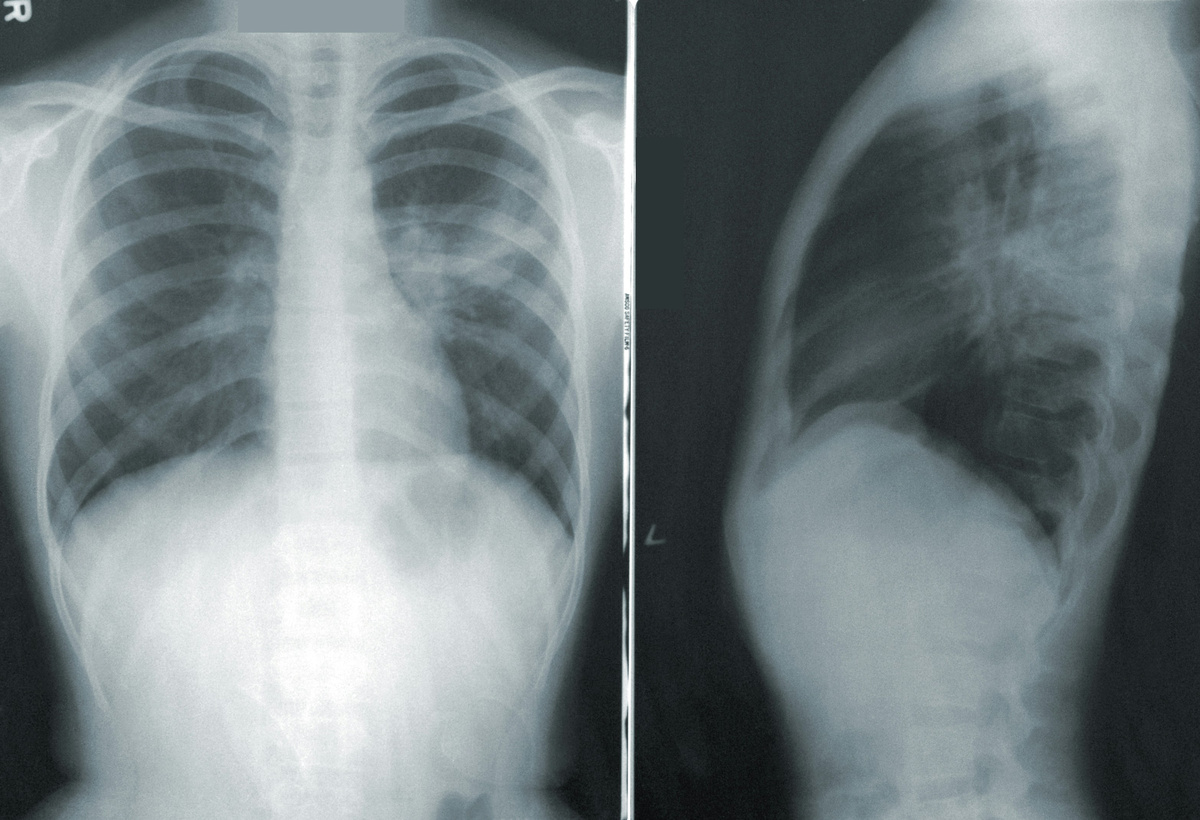

Роспотребнадзор назвал озноб и температуру основными симптомами пневмонии

Кашель, высокая температура, озноб и затрудненное дыхание являются основными симптомами пневмонии. Об этом РИА «Новости» сообщили в пресс-службе Роспотребнадзора.

В ведомстве пояснили, что пневмония — это воспаление легочной ткани, которое чаще всего вызывают бактерии, вирусы или грибы. Она может быть как самостоятельным заболеванием, так и осложнением после гриппа, кори или коклюша.